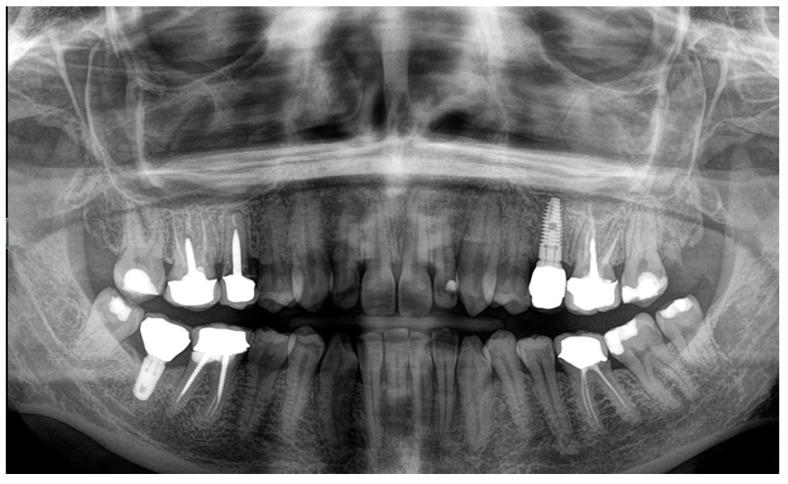

Medication-related osteonecrosis of the jaw (MRONJ) is a drug complication that can occur in patients taking antiresorptive or antiangiogenic drugs. Although it is a well-documented disease, there is no widely accepted treatment. However, several therapeutic approaches have been proposed. The surgical approach in many advanced cases appears inevitable; however, the results are not yet defined and predictable. This study aimed to propose a combined surgical approach with a piezoelectric device and laser (Er:YAG for bone ablation and Nd:YAG laser for photobiomodulation) in a young patient with breast cancer and bone metastasis under denosumab treatment, affected by spontaneous stage 3 MRONJ with maxillary sinus involvement. The patient under study reported no post-operative discomfort, with painkiller intake limited to the day after surgery. Total mucosal healing was observed without recurrences for more than 4 years after surgery. According to the results of our preliminary study, a combined surgical approach using a piezoelectric device and laser therapy is effective in managing patients affected by MRONJ, leveraging the clinical and biological advantages of these different techniques.

药物相关性颌骨坏死(MRONJ)是一种可发生于服用抗吸收或抗血管生成药物患者的药物并发症。尽管它是一种有充分文献记载的疾病,但尚无广泛接受的治疗方法。然而,已经提出了几种治疗方法。在许多晚期病例中,手术方法似乎不可避免;然而,其结果尚未明确且可预测。本研究旨在为一名接受地诺单抗治疗、患有乳腺癌和骨转移、受自发性3期MRONJ累及上颌窦影响的年轻患者,提出一种结合压电装置和激光(用于骨消融的铒:钇铝石榴石激光和用于光生物调节的钕:钇铝石榴石激光)的联合手术方法。研究中的患者术后无不适,止痛药服用仅限于术后当天。术后观察到黏膜完全愈合,4年多无复发。根据我们初步研究的结果,使用压电装置和激光治疗的联合手术方法在治疗受MRONJ影响的患者方面是有效的,利用了这些不同技术的临床和生物学优势。